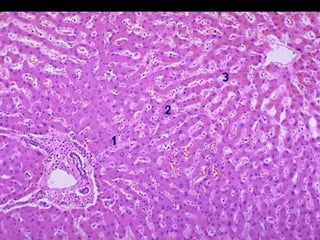

    Le foie : nécrose hépatocytaire centrolobulaire,

dilatation sinusoïdale.

Nécrose centrolobulaire

partiellement

hémorragique,

systématisée autour

des veines dilatées (V),

avec respect des zones

périportales . Espace

porte (EP).

Nécrose centrolobulaire partiellement hémorragique, systématisée autour desveines dilatées (V), avec respect des zones périportales . Espace porte (EP).